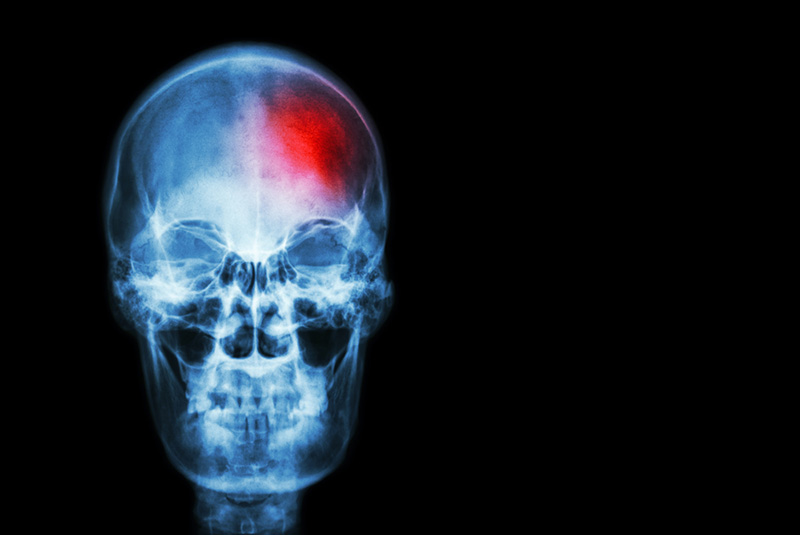

แพทย์สหรัฐฯ เผยรายงานวิเคราะห์ COVID-19 อาจเป็นสาเหตุให้วัยผู้ใหญ่ตอนต้น เกิดโรคหลอดเลือดสมองเฉียบพลัน แม้ไม่มีอาการป่วยหนัก อันตรายถึงชีวิต หากช่วยไม่ทัน

เมื่อวันที่ 23 เมษายน 2563 สำนักข่าวซีเอ็นเอ็น รายงานว่า คณะแพทย์จากโรงพยาบาล Mount Sinai Health System ในนิวยอร์ก สหรัฐอเมริกา ได้เผยรายงานการศึกษา ที่ตีพิมพ์ลง New England Journal of Medicine พบหลักฐานเพิ่มเติมว่า COVID-19 สามารถทำให้เลือดจับตัวเป็นก้อนในลักษณะที่ผิดปกติ และก่อให้เกิดโรคหลอดเลือดสมอง ในวัยผู้ใหญ่ตอนต้น ช่วงอายุประมาณ 30 และ 40 กว่าปี ซึ่งมักจะป่วยโควิด 19 แบบไม่แสดงอาการป่วยรุนแรง

ดร.โทมัส อ็อกเลย์ ศัลยแพทย์โรคประสาท และเพื่อนร่วมทีม เผยข้อมูลอ้างอิงจากคนไข้จำนวน 5 ราย ที่พวกเขาทำการรักษา ทั้งหมดอายุไม่ถึง 50 ปี ทุกคนป่วยโควิด 19 แบบไม่มีอาการรุนแรง หรือไม่มีอาการเลย แต่ดูเหมือนว่าเชื้อไวรัสโคโรนา จะทำให้เกิดลิ่มเลือดเพิ่มขึ้นในหลอดเลือดแดงใหญ่ นำไปสู่โรคหลอดเลือดสมองอย่างรุนแรง อาการเฉียบพลันอันตรายถึงชีวิต

ดร.โทมัส กล่าวว่า "รายงานของเราแสดงให้เห็นว่า เกิดโรคหลอดเลือดสมองเฉียบพลัน ในผู้ป่วยอายุน้อย (ที่ไม่ใช่ผู้สูงอายุ) เพิ่มขึ้นเป็นจำนวนเจ็ดเท่าจากปกติ ในช่วงสองสัปดาห์ที่ผ่านมา ผู้ป่วยเหล่านี้ ส่วนใหญ่ไม่มีประวัติการเจ็บป่วย หรือการรักษาทางการแพทย์มาก่อนหน้านี้ และอยู่ที่บ้านด้วยอาการที่ไม่รุนแรง หรือไม่แสดงอาการ แต่ทั้งหมดมีผลทดสอบโควิด 19 เป็นบวก"

ทั้งนี้ ทางทีมแพทย์ยังได้เผยว่า ผู้ป่วยอายุน้อยส่วนใหญ่ลังเลใจที่จะแจ้งหน่วยฉุกเฉิน ในกรณีที่สงสัยว่าอาจจะติดเชื้อ เนื่องจากความกังวลถึงความโกลาหลที่โรงพยาบาล ในการรับมือกับผู้ป่วยโควิด 19 ที่มีอาการรุนแรง โดยในจำนวนผู้ป่วยของพวกเขา พบว่ามีจำนวน 2 ราย ที่โทร. แจ้งรถฉุกเฉินของโรงพยาบาลล่าช้า ทำให้เกิดอาการโรคหลอดเลือดสมอง ซึ่งมันไม่ใช่เรื่องปกติที่คนอายุน้อยจะเกิดโรคนี้ โดยเฉพาะอย่างยิ่งกับเส้นเลือดใหญ่ในสมอง

ดร.โทมัส กล่าวเสริมว่า โรคหลอดเลือดสมองในเส้นเลือดใหญ่ ก่อให้เกิดความเสียหายอย่างรุนแรง หากไม่ได้รับการรักษาโดยทันที ผู้ป่วยอาจจะถึงขั้นเสียชีวิต หรืออาการวิกฤต เนื่องจากเซลล์สมองจะตาย เมื่อขาดการไหลเวียนของเลือด และยิ่งหลอดเลือดถูกปิดกั้นนานเท่าไร ความเสียหายในสมองก็จะยิ่งมากขึ้นเท่านั้น การรักษาอย่างรวดเร็วจึงมีความสำคัญ โดยการรักษาที่มีประสิทธิภาพมากที่สุดสำหรับหลอดเลือดขนาดใหญ่ คือการกำจัดลิ่มเลือด แต่ต้องทำภายใน 6 ชั่วโมง หรือนานไม่เกิน 24 ชั่วโมง